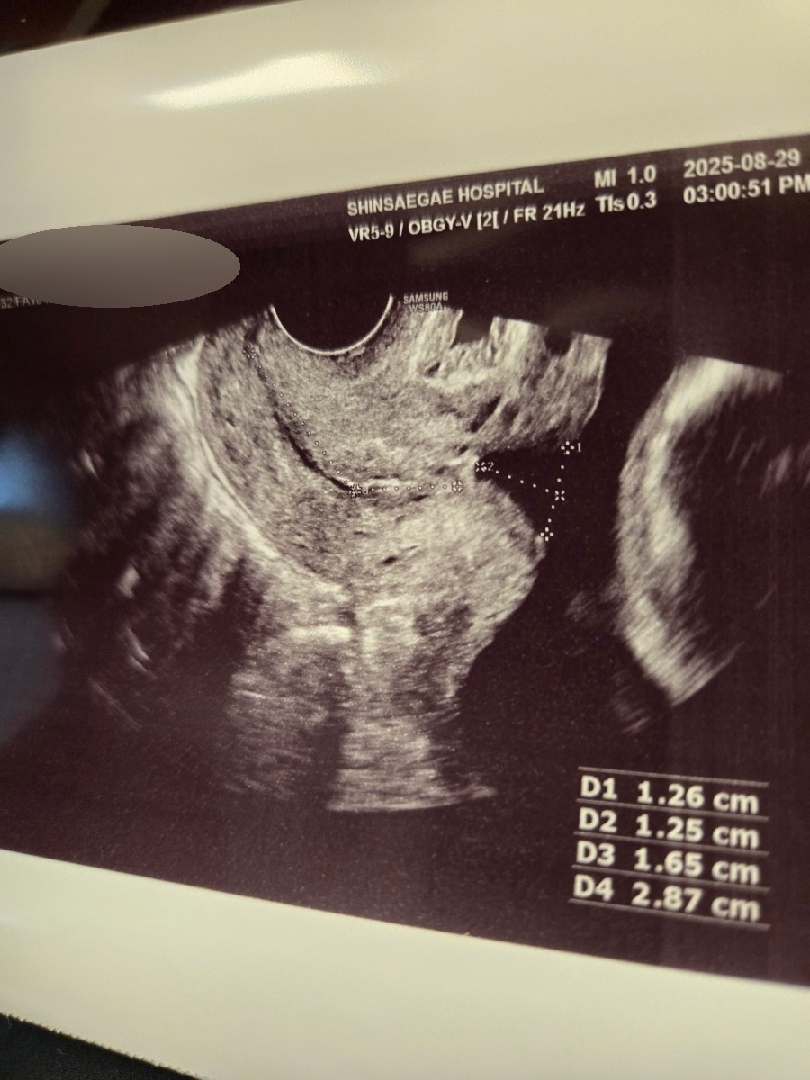

제 자궁경부길이 좀 봐주세요

병원에서 정확히 말을 안해줘서요. 대략 3센치인 걸 알고 있는데 맞을까요?? (원장님이 3정도면이라고 말씀하셨음) 추가) 제가 인터넷 찾아본 바로는 디3와 디4를 더하는 값이 경부길이인데 그렇게 하면 4점대가 넘어서요. 당장 급한 것도 아니고 성격상 병원에 계속 전화하는게 신경 쓰여서 자유게시판에 묻습니다.(개인병원 아니라서 까다롭) 아직 병원 갈 날도 멀었거든요.😊

제가알기론 저 D1234 가 양수량 체크하는걸로 알고있는데 D3 D4 더한값이 자궁경부길이레요??? 자궁경부길이는 cervical lenght 라고하는데 받은 초음파사진에 cervical 적힌거없을까요??? 저 20주 정밀초음파때 3.54cm 였는데 정상이라 하셨거든요!!